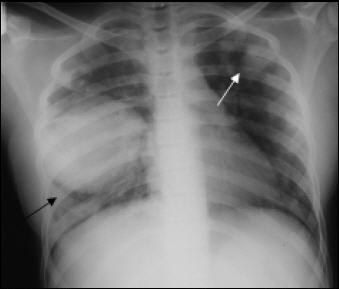

Akciğer kist hidatiği: Kist çoğunlukla sağ akciğere yerleşir. Uzun yıllar hiçbir belirti vermeden sessizce ilerleyebilir. Bazı durumlarda ise kist bir bronşa açılarak, kist sıvısı öksürükle birlikte dışarı atılabilmektedir. Hastalığın başlangıç aşamasında göğüs ağrıları, öksürük ve kanlı balgam gibi dikkat çekici belirtiler ortaya çıkar. Lakin çoğunlukla bu belirtiler pek önemsenmez Uzun bir müddet sonra ise deride bazı kızarık döküntülere rastlanabilir. Astım bronşite benzeri solunum güçlükleri ortaya çıkabilir. Kist bazı nadir durumlarda plevra boşluğuna açılmaktadır. Böyle durumlarda göğüste şiddetli bir ağrı, nefes darlığı, morarma ve şok gibi ağır bozuklukları ortaya çıkabilir.